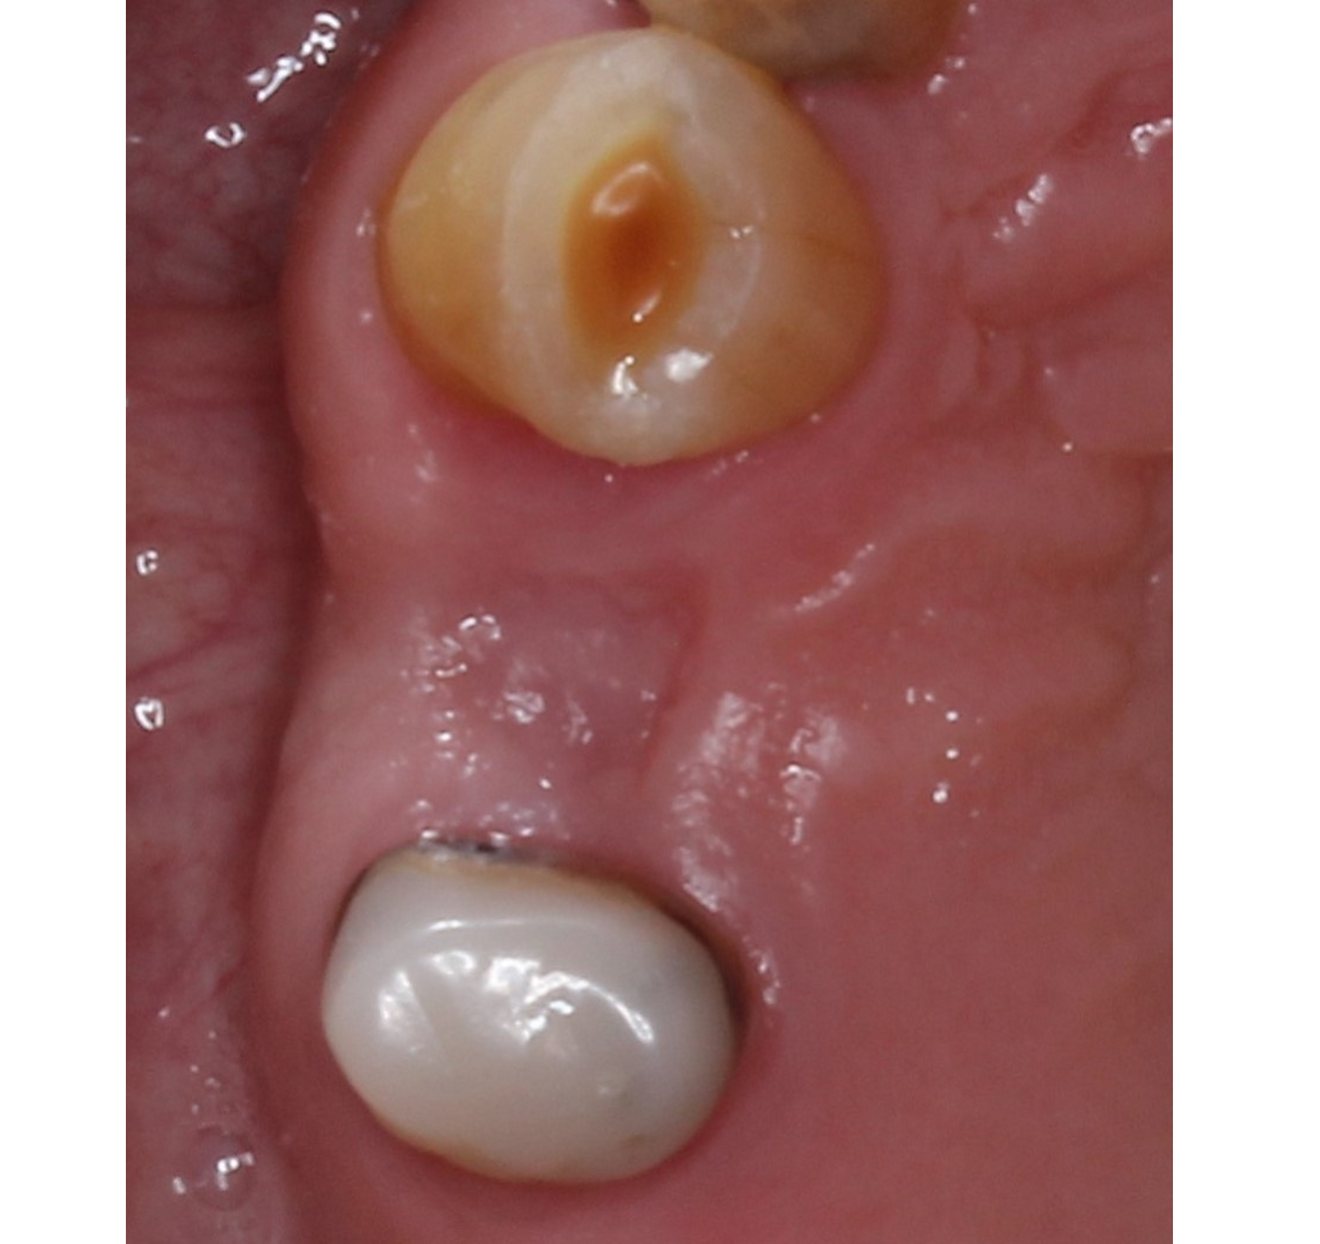

A male patient presented in our dental office with a severely broken maxillary right first premolar (tooth #14) that had been designated for extraction a number of years before. The tooth immediately distal (tooth #15) was also in need of substantial dental treatment (Figs. 1 & 2). The patient had hypertension that was controlled with anti-hypertensive medication, but was otherwise medically fit. He intended to have the colour of his anterior teeth improved, but wished to address the issues on his maxillary right side first.

Fig. 2: Pre-op situation, showing the maxillary right first premolar with a poor restorative prognosis.